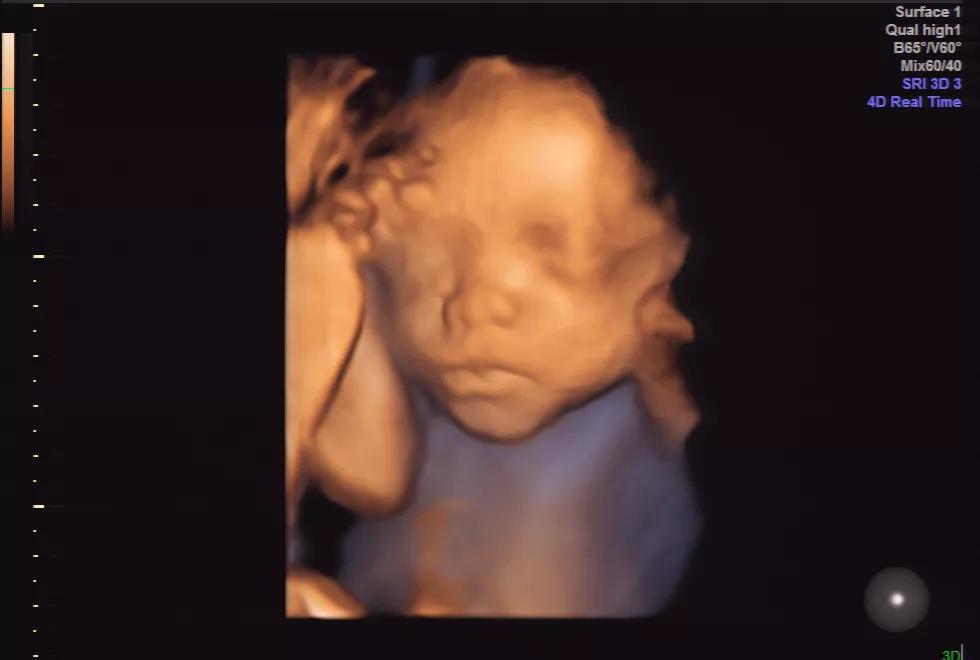

济南艾玛妇产医院超声专家朱爱莲医生表示:日渐成熟的超声诊断技术(四维彩超),已成为降低新生儿出生缺陷率的重要途径,至少70%的出生缺陷是可以通过预防措施控制的。